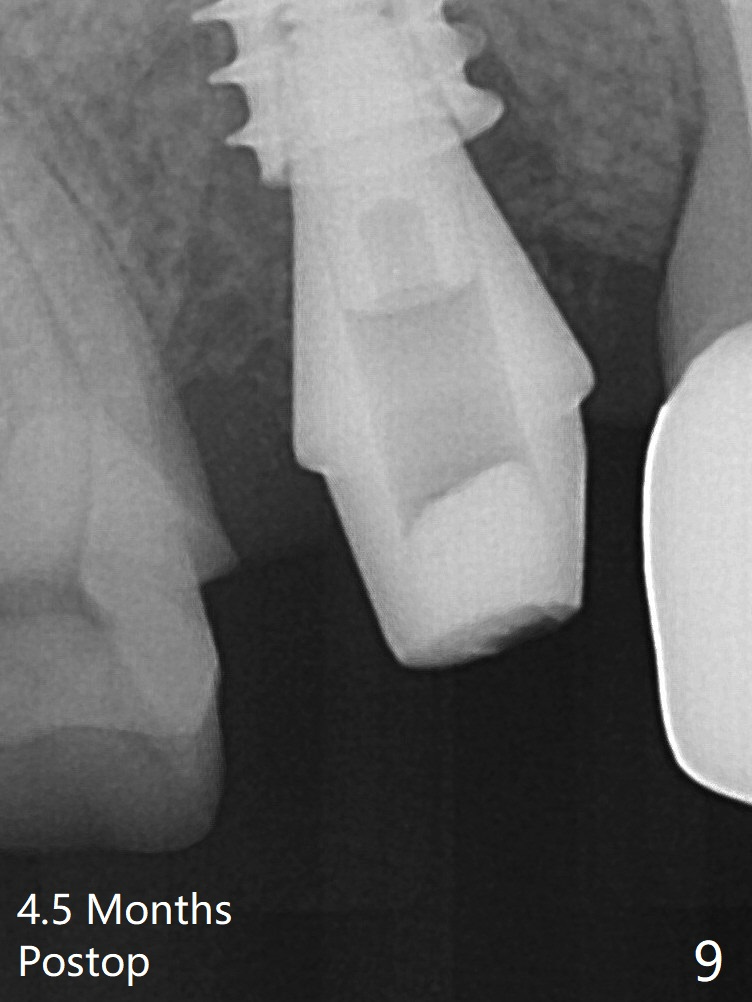

To reduce the gap and periimplantitis, a 5x11 mm IBS implant is placed with insertion torque > 50 Ncm after further osteotomy using Magic Drills (Fig.4). Following placement of 5.5x4(4) mm abutment (A), a splinted provisional is fabricated at #3 and 4. The provisional is stable 3 months postop (Fig.7). Bone graft appears to remain between the implant fins (arrows). The bone density of the bone graft between the implant fins increases 4.5 months postop (Fig.9). The bone density appears to reach the normal value (same as that of the nearby bone) 1 year 3 months post cementation (Fig.11).